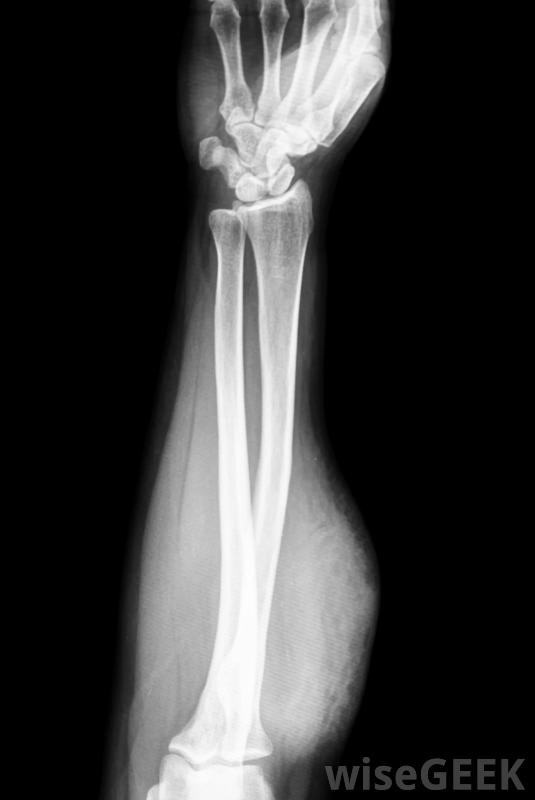

骨化性肌炎是骨骼开始在肌肉内生长的一种不寻常的情况,有时也被称为异位骨化。这种情况可以通过x射线图像来识别,这些图像将显示肌肉内和不应该出现骨骼的位置的骨沉积。治疗方法取决于骨生长的位置、潜在原因和患者的...

骨化性肌炎是骨骼开始在肌肉内生长的一种不寻常的情况,有时也被称为异位骨化。这种情况可以通过x射线图像来识别,这些图像将显示肌肉内和不应该出现骨骼的位置的骨沉积。治疗方法取决于骨生长的位置、潜在原因和患者的年龄等因素。

骨化性肌炎可在X光片上显示有几个原因可以导致骨化性肌炎。在某些人中,它是遗传性的。人们会在他们的肌肉中进行性骨生长,并且随着时间的推移,这种情况在一些病人中可能会致命,在一种被称为进行性骨化纤维发育不良(FOP)的罕见遗传病中,对病人组织的损害会导致骨的生长,随着时间的推移,会导致全身广泛的异位骨化